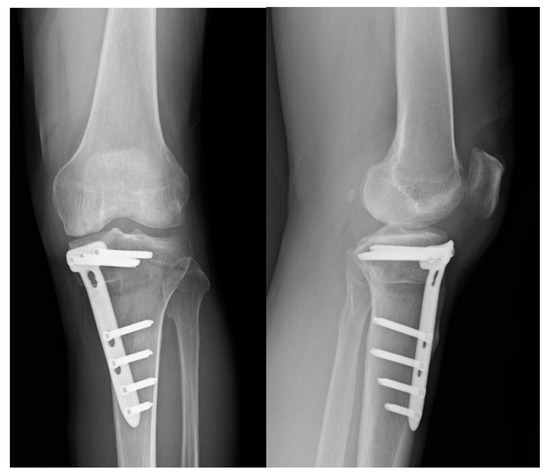

2.2. Surgical Technique